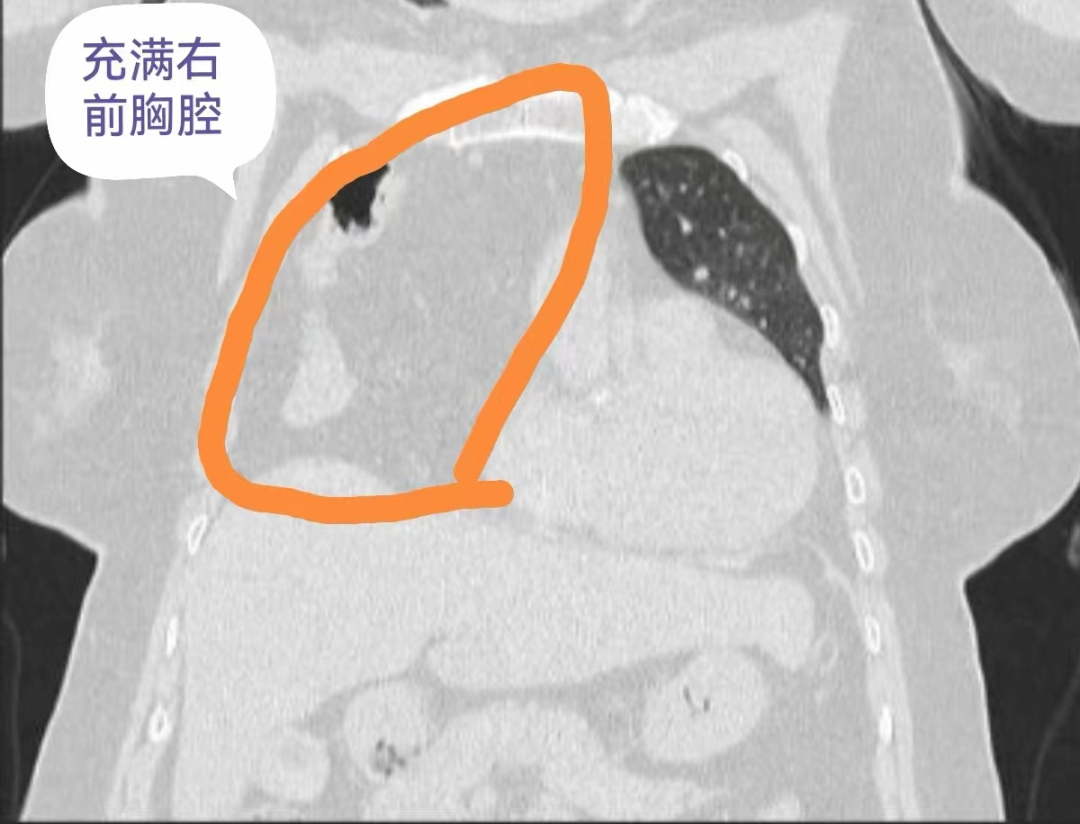

在我们体内,有许多看似平凡却至关重要的器官,它们默默合作,保障我们的生命活动能够持续且稳定地进行。其中,膈肌就是这样一个不可或缺的角色,它如同一道屏障,将胸腔和腹腔分隔开来,同时也参与呼吸的过程。然而,当膈肌出现问题时,一种名为膈疝的疾病就可能悄然发生,给我们的生活和工作带来诸多困扰,甚至威胁到我们的生命。 8年前 患者刘奶奶被当地医院 诊断为“冠心病” 一直口服药物治疗 效果不明显 近日,刘奶奶(75岁)来到贵州航天医院做了胸部CT、冠脉造影等检查,经过心血管内科、呼吸与危重症医学科、心胸外科、影像科等多学科会诊讨论,确诊并没有冠心病,而是因为有“膈疝”导致她的一系列症状。而且,刘奶奶的膈疝还非常严重,腹部的肠管和网膜已经“跑”到右侧胸腔顶部去了,还占据了整个右侧前胸腔,难怪会出现那么明显的症状。通常这类严重的膈疝多采用开放手术,需要至少15厘米长的切口。 贵州航天医院心胸外科陈光春主任团队经过精心术前准备,为刘奶奶行胸腔镜下微创膈疝修补术,仅仅在胸壁打了4个0.5-1.0cm小孔,就成功将“疝”移到右侧胸腔的肠管和网膜等腹腔内容物送回了腹腔,并将膈肌缺损的部位缝合加固,手术圆满成功。术后4天,刘奶奶各项指征恢复正常出院,她发现之前那些活动后胸闷、心悸、气促、呼吸困难等症状都消失了,一口气能走上四五楼都毫无压力。 刘奶奶的这个症状在术后得到缓解了,她感叹“这个手术过程,仅仅在胸部打了几个小“洞洞”就完成了,术后恢复还这么快!感谢航天医院的精心诊治!” 科 普 什么是隔疝? 日常说的“疝气”,一般是指在腹部体表有异常包块,用手按压的时候包块可以进入腹腔,认为包块内有气,所以称为疝气。 其实,疝是指人体内脏器或组织离开其正常位置跑到了另一地方,疝不仅会出现在体表。比如:腹腔脏器还会通过和胸腔之间的膈肌薄弱部位到达胸腔,称之为“膈疝”,此时往往因为压迫心肺而出现心悸、气促、呼吸困难、胸痛等症状而容易被误诊为心脏病或肺病。 治疗隔疝 手术是最佳治疗方法 膈疝的手术治疗方法主要包括膈疝修补术。对于先天性膈疝,如果临床无明显症状,可以等到患者年龄稍大后再进行手术治疗。 但如果出现肠梗阻或幽门梗阻等症状,或者出现心、肺压迫症状,如心悸、气促、咳嗽、胸闷、呼吸困难、发绀等,不论年龄大小都应尽早进行手术治疗。 术后注意事项 膈疝手术后的患者,在饮食方面,应遵循少食多餐、细嚼慢咽的原则,避免暴饮暴食和进食过快。同时,应选择易消化、营养丰富的食物,避免进食辛辣、油腻等刺激性食物,以免给刚刚修复的膈肌带来额外的负担。 在休息方面,患者应保持充足的睡眠和休息,避免过度劳累和剧烈运动。适度的活动可以促进血液循环和新陈代谢,有助于身体的康复,但过度活动则可能导致伤口裂开或复发。 此外,术后患者还需定期进行复查和随访,以及时发现并处理可能出现的并发症或复发情况。医生会根据患者的具体情况制定个性化的康复计划,帮助患者尽快恢复健康。 贵州航天医院心胸外科简介 心胸外科是诊治疾病种类较为复杂,专科性非常强的一门学科。心胸外科手术难度大,风险高,对设备和配套要求也高,大众对心胸外科经常会存有误解,误认为心胸外科只是看胸外面的病,这就很容易让人联想到乳腺疾病等,其实胸外科主要看的是胸腔内的病,主要是食管、气管及肺上的疾病。如食管囊肿、食管平滑肌瘤、贲门失迟缓症、严重的反流性食管炎、食管裂孔疝、自发性食管破裂、食管、气管瘘、食管癌、食管胃交界处癌(贲门癌)、肺大疱(有时破裂引起自发性气胸)、肺脓肿、肺隔离症、肺结核球、肺结节等需到心胸外科就诊。 心胸外科导航 贵州航天医院呼吸综合楼003诊室 住院病区:呼吸综合楼4楼 门诊坐诊时间 每周一至周五 (08:00—12:00;14:00—17:00) 咨询电话 住院病区咨询电话:27677360(医生办公室);0851-27677732(护士站) 心胸外科专家 精彩推荐 1.【义诊预告】6月1日,贵州航天医院多名资深儿科专家开展义诊活动 2.【航医科普】贵州航天医院前列腺增生微创治疗——经尿道前列腺钬激光剜除术(HoLEP),为您解决“男”言之隐